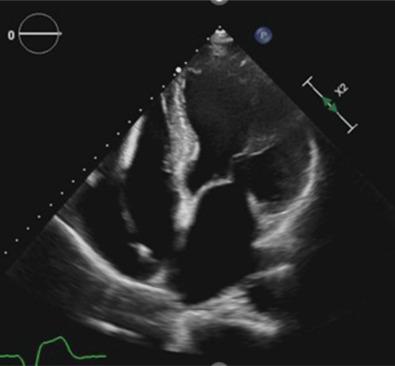

Sarcoidosis is a chronic inflammatory condition of uncertain origins, affecting multiple organs and characterized by the formation of granulomas. Cardiac involvement, known as cardiac sarcoidosis (CS), occurs in 5%-10% of cases and can lead to heart failure, arrhythmias, and sudden death. Distinguishing CS from other heart conditions poses a significant challenge. However, improved diagnostic techniques such as cardiac magnetic resonance (CMR) and positron emission tomography combined with computed tomography (CT) have enhanced recognition rates, replacing invasive procedures like endomyocardial biopsy. Clinical guidelines have further facilitated diagnosis. This case report underscores the diagnostic complexity of CS and highlights the emerging role of contrast-enhanced cardiac CT as a viable alternative to CMR, particularly in patients with contraindications to CMR.